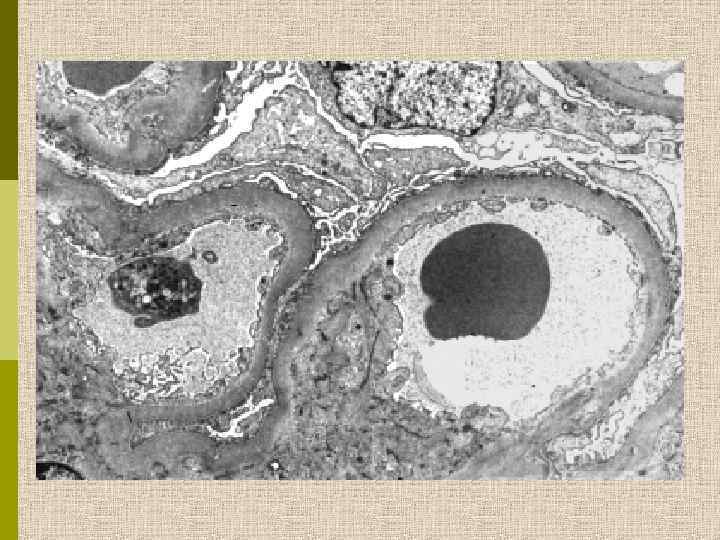

МОРФОЛОГИЧЕСКИЕ ИЗМЕНЕНИЯ ПРИ ДИАБЕТИЧЕСКОЙ НЕФРОПАТИИ Основные варианты - диабетический гломерулосклероз с узелками Kimmelstiel-Wilson - диффузный мезангиальный гломерулосклероз Характерные признаки Утолщение ГБМ; артериолярный гиалиноз; аневризматические капилляры; капсулярные капли; фибриновые шапочки; атрофия канальцев; инфильтрация, расширение и склероз интерстиция; линейные отложения иммуноглобулинов

PAS Узелковый гломерулосклероз (болезнь Киммельстиля-Вильсона) у больного с длительным течением сахарного диабета. Выраженное утолщением артериолы – типичный гилиновый артериолосклероз, наблюдаемый при сахарном диабете.